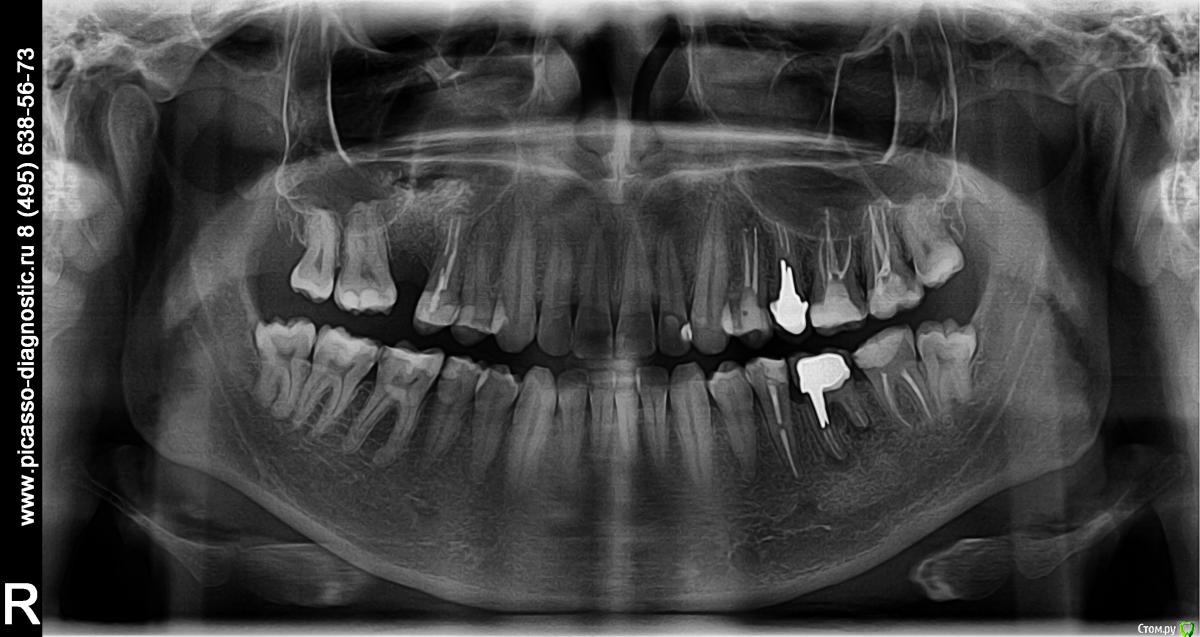

Bill_Lance Опубликовано 11 апреля, 2017 Поделиться Опубликовано 11 апреля, 2017 14 зуб - верхняя челюсть, первый после левого клыка. Мертвый. Рядом зуб с коронкой, просто для ориентации по ортопанораме.Давно залечили кариес, но, на кровне корней какая-то бяка осталась. Темная область на рентгене.Осенью 2016-го стало поболевать. Не сильно, жить никак не мешает, но ощущение приходит и уходит, и в целом есть.Врач объяснил так. По памяти. Толи не все вычистили, толи и нельзя было вычистить, но вообщем, это осталось на роль иммунитета. Иммунитет не подавил.Говорит, что по снимку видит, что по снимку видит, что можно сделать резекцию верхушки корня, все вычистить. Другой врач сказал, что после резекции я лишусь зуба в течении нескольких лет. Предлагает провести профилактическую чистку ротовой полости. Говорит боль уйдет. Я не хочу лишаться зуба - у меня не приживуются импланты и вообще их ставить мне нельзя. Аутоимунный ответ. Но и в простую профилактическую чистку я не верю. Снять налет это одно. Удалить бактерии из костной ткание это другое. Что можно сделать что бы сохранить зуб без удаления верхушки корня? Неужели нельзя убить болезнетворную микрофлору и вывести оттуда все их продукты жизнедеятельности и продукты распада тканей - все, что токсично для окружающих здоровых тканей, - без удаления части корня зуба? Ортопанорама челюсти с диска.http://www.mediafire.com/view/gnnimxbrmn0va4n/p20170112_163911_0000.bmp https://www.virustotal.com/ru/file/4f6ddad1a30f05489dfb0b451f9e55edec333a9e93f035eab9da79469c28b455/analysis/1491912668/- проверка на вирусы - чисто. В приложенном файле сжато в jpg, качество соответственно хуже. Ссылка на комментарий

St. Опубликовано 11 апреля, 2017 Поделиться Опубликовано 11 апреля, 2017 Если слева, то зуб 24.По снимку качество пломбировки каналов нормальное. Зато с нижним левым под коронкой проблемы ( воспаление на корнях) Ссылка на комментарий

Bill_Lance Опубликовано 20 апреля, 2017 Автор Поделиться Опубликовано 20 апреля, 2017 (изменено) Появился еще один рентген. Проблемный зуб на снимке - самый правый полностью видный. Под корнем видна небольшая темная область. http://i89.fastpic.ru/big/2017/0421/a0/fd4bdcff62fc845f92e7786362e58aa0.jpg Изменено 20 апреля, 2017 пользователем Bill_Lance Ссылка на комментарий

Pan Опубликовано 22 апреля, 2017 Поделиться Опубликовано 22 апреля, 2017 24 зуб. такая "тёмная область" не является показанием для проведения хирургических вмешательств (резекций). Ссылка на комментарий